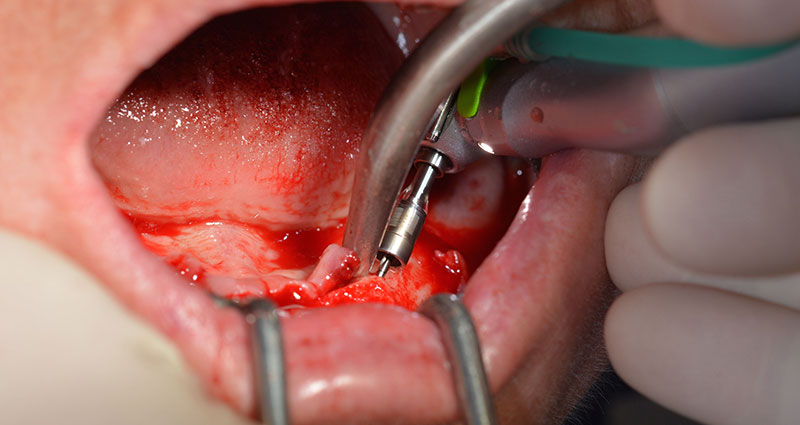

Le protocole chirurgical préconisé pour les implants utilisés (SKY, Bredent Medical) précise une vitesse de rotation de 1.200 tr./min. pour le pré-forage (Fig. 7 - 9).

Ceci correspond à la position suivante prédéfinie dans l'Implantmed. Nous voyons ici le contre-angle W&H tenu à un angle de 45° par rapport à la crête dans la région de 45 afin de préserver le nerf mentonnier. Le trou mentonnier sert de repére anatomique à tous les forages de cette région. Les forages suivants ont été effectués à la vitesse réduite de 300 tr./min. (Fig. 10 et 11).